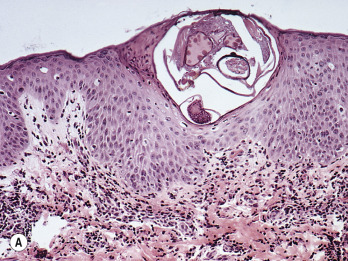

The adult mite is

-mm long and has a flattened, oval body with wrinkle-like, transverse corrugations and eight legs ( Fig. 15.1 ). The front two pairs of legs have claw-shaped suckers and the two rear pairs end in long, trailing bristles. The digestive tract fills a major portion of the body and is readily observed when the mite is seen in cross-section of histologic specimens ( Fig. 15.2A ).

Infestation begins when a fertilized female mite arrives on the skin surface. Within an hour, the female excavates a burrow in the stratum corneum (dead, horny layer) ( Fig. 15.2B ). During the mite’s 30-day life cycle, the burrow extends from several millimeters to a few centimeters in length. The burrow does not enter the underlying epidermis except in the case of hyperkeratotic Norwegian scabies, a condition in which scaly, thick skin develops in intellectually disabled, immunosuppressed, or elderly patients in the presence of thousands of mites. Eggs laid at the rate of two or three a day ( Fig. 15.3 ) and fecal pellets (scybala) are deposited in the burrow behind the advancing female. Scybala are dark, oval masses that are seen easily with the eggs when burrow scrapings are examined under a microscope. Scybala may act as an irritant and may be responsible for some of the itching. The larvae hatch, leaving the egg casings in the burrow, and reach maturity in 14 to 17 days. The adult mites copulate and repeat the cycle. Therefore, 3 to 5 weeks after infestation, there are only a few mites present. This life cycle explains why patients experience few, if any, symptoms during the first month after contact with an infested individual. After a number of mites (usually less than 20) have reached maturity and have spread by migration or the patient’s scratching, the initial, minor, localized itch evolves into intense, generalized pruritus.